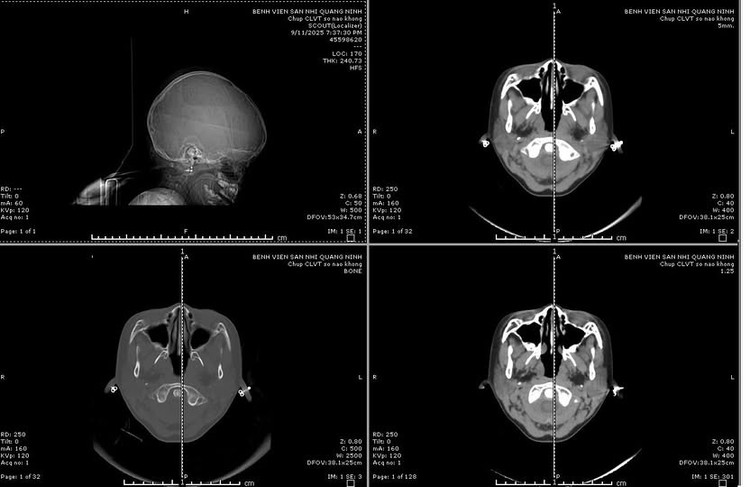

Sau khi tiếp nhận, bệnh viện đã kích hoạt quy trình báo động đỏ toàn viện, trẻ được các bác sĩ đã nhanh chóng xử trí hồi sức, cấp cứu suy hô hấp, cấp cứu ngừng tim, ngừng tuần hoàn, chăm sóc tích cực và thực hiện các cận lâm sàng. Kết quả cho thấy trẻ bị vỡ xương sọ phức tạp, kèm theo chảy máu và dập não phức tạp.

Các bác sĩ chuyên ngành ngoại thần kinh nhi của Bệnh viện Sản Nhi đã tiến hành phối hợp hội chẩn liên viện với chuyên gia ngoại thần kinh của Bệnh viện Đa khoa tỉnh; Trẻ được chẩn đoán bị xuất huyết nội sọ do chấn thương sọ não, tăng áp lực nội sọ, suy hô hấp và nhanh chóng được chuyển phòng mổ chỉ định mổ cấp cứu chấn thương sọ não.

Hình ảnh phim chụp chấn thương sọ não nặng - Ảnh BVCC